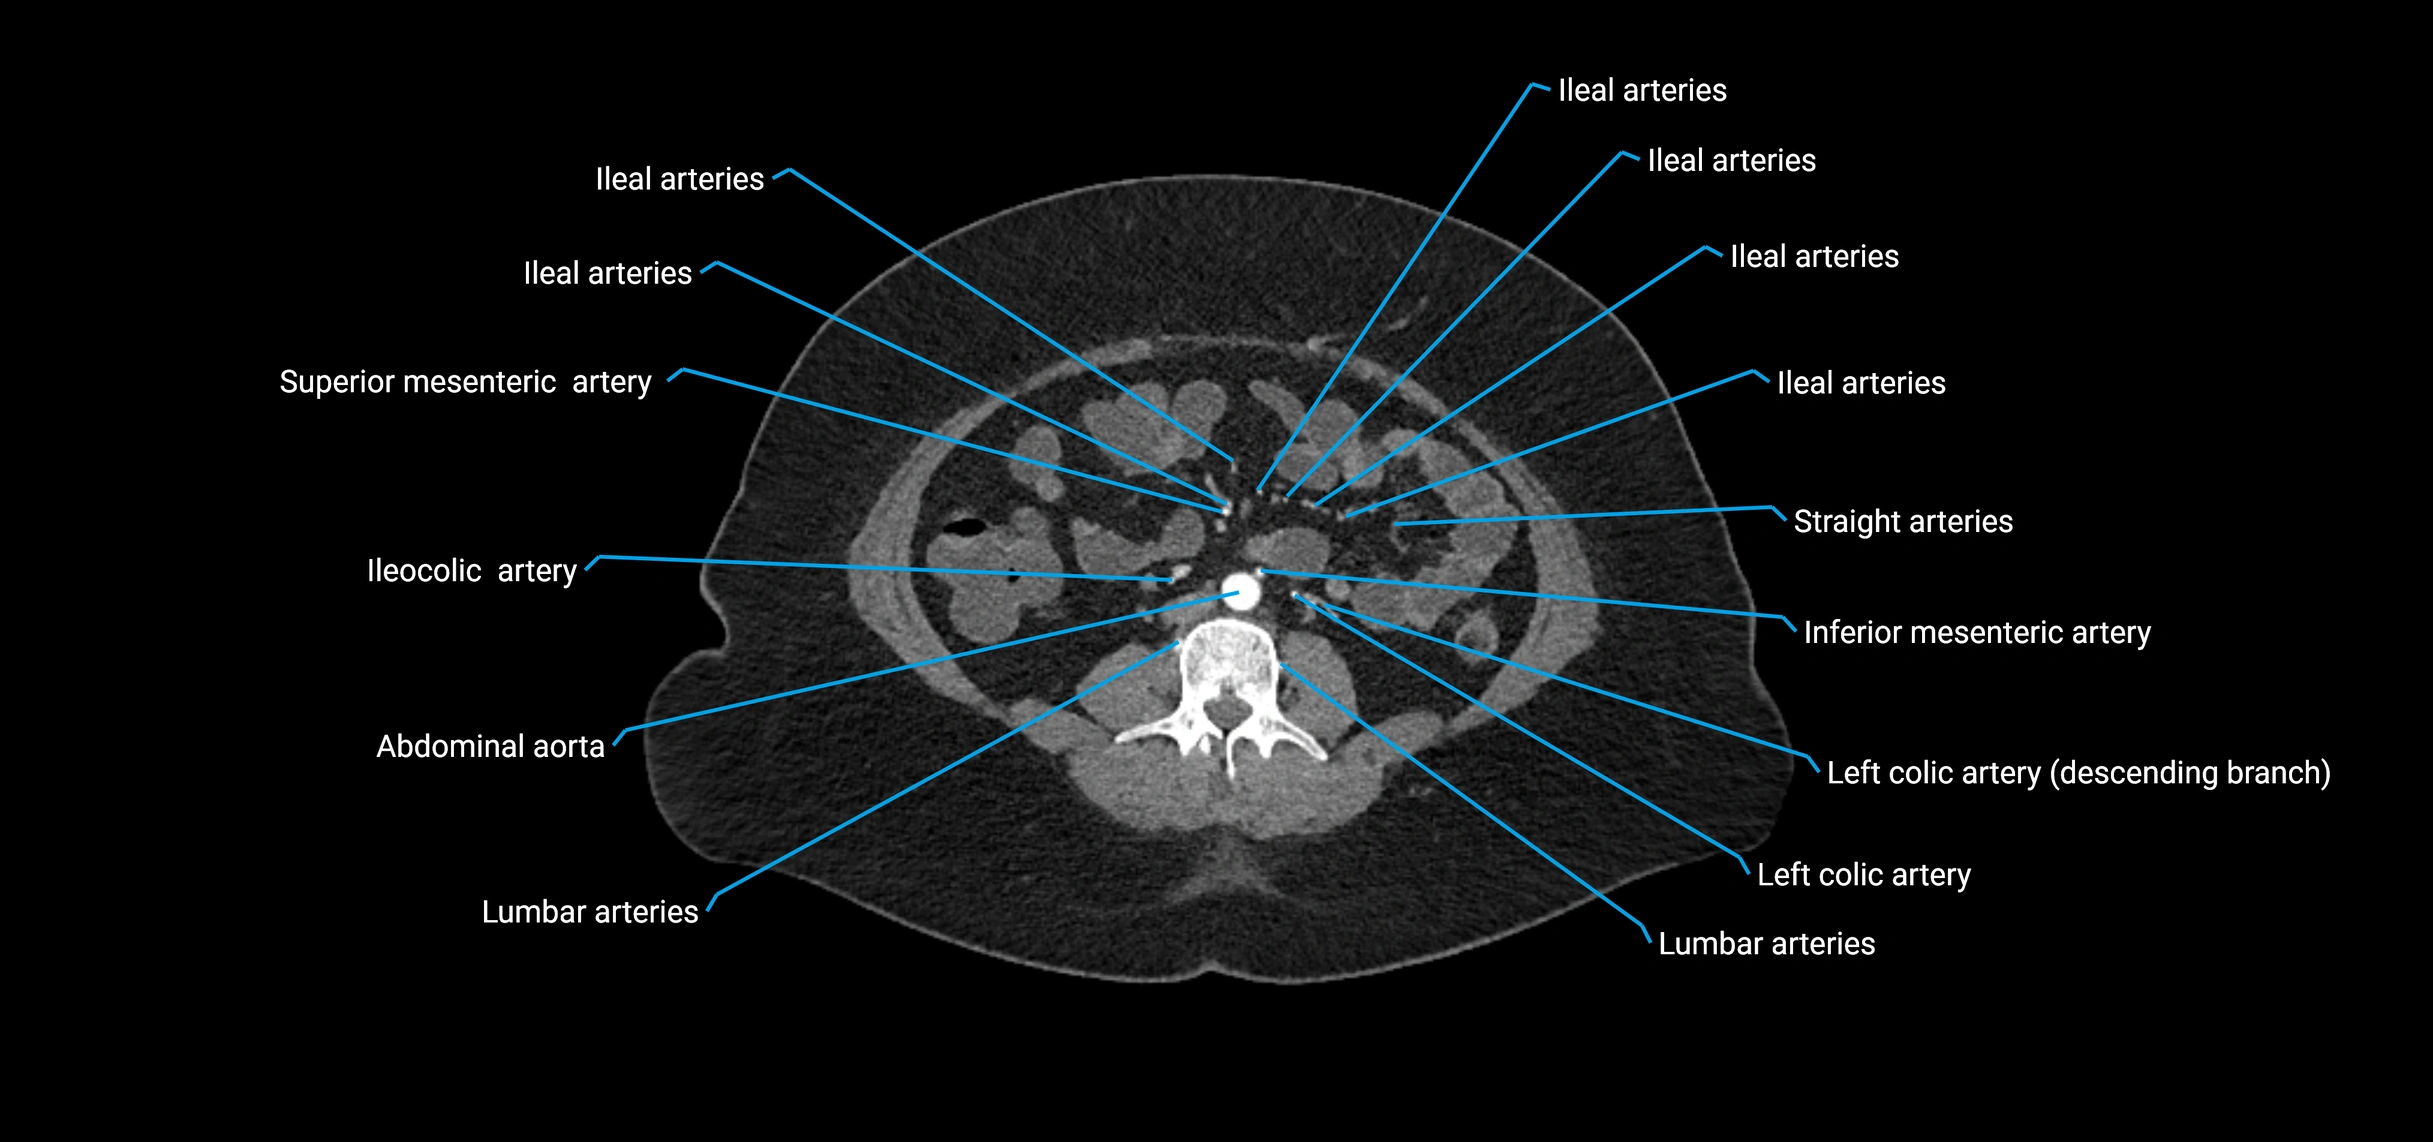

Contrast-enhanced CT (CTA):

• Gold standard for abdominal aortic imaging

• Provides excellent detail of lumen, wall, aneurysm, thrombus, and branch vessels

• Multiplanar and 3D reconstructions help in aneurysm measurement, stent graft planning, and dissection evaluation